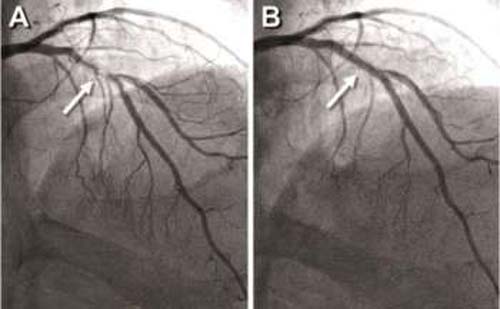

Conforme explica o cardiologista intervencionista e hemodinamicista Leilton Luna, o padrão ouro no tratamento de doenças cardiovasculares é o implante de “stents” coronarianos em vasos sanguíneos obstruídos. Eles são famosos pela sua aparência, semelhante a pequenas “molas” que o especialista coloca nas artérias do coração (figura) para desobstruir as placas de gordura.

O stent é uma malha que, levada ao local obstruído, se expande